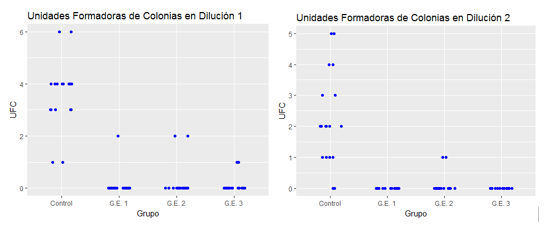

Grupo control- Muestras obtenidas de las cámaras de implantes sin compuestos químicos. Todas las placas sembradas con las dos diluciones mostraron desarrollo de colonias. Las muestras sembradas de la primera dilución mostraron: 2 placas con más de 3.000 UFC, 2 placas con 6 UFC, 8 placas con 4 UFC, 6 placas con 3 UFC, 2 con 1 UFC. Las muestras sembradas de la segunda dilución: 2 placas con más de 100 UFC, 2 placas con 5 UFC, 2 placas con 3 UFC, 2 con 4 UFC,6 con 2 UFC,4 con 1 UFC y 2 placas sin crecimiento.

GE1- Muestras obtenidas de las cámaras de implantes con hidróxido de calcio y metilcelulosa. De las placas sembradas de la primera dilución en una placa desarrollaron 2 UFC, las segundas diluciones no mostraron desarrollo de microorganismos.

GE2- Muestras obtenidas de las cámaras de implantes con yodoformo y metilcelulosa. Dos placas sembradas de la primera dilución de las muestras tuvieron desarrollo con 2 UFC. Dos placas sembradas de la segunda dilución de las muestras tuvieron desarrollo con 1 UFC.

GE3- Muestras obtenidas de las cámaras de implantes con mezcla de hidróxido de calcio, yodoformo y metilcelulosa. Dos placas sembradas de la primera dilución tuvieron desarrollo con 1 UFC. Las muestras sembradas de la segunda dilución no tuvieron desarrollo.

Los resultados de este estudio demuestran que existió una filtración de microorganismos hacia la cámara interna del implante. Se desarrollaron colonias en todas las placas sembradas con tomas sin agentes químicos (100%). La colocación de los agentes químicos introducidos en las cámaras de los implantes resultó favorable ya que disminuyeron el número de unidades formadoras de colonias de todas las muestras, tanto en la primeras diluciones (95%- GC1 y 90%- GC2 y GC3) como en las segundas diluciones (90%-GC2 y 100% -GC1 y GC3) obteniéndose los resultados más exitosos con la utilización de la mezcla de hidróxido de calcio y metilcelulosa y en combinación con el yodoformo y metilcelulosa.

El análisis descriptivo de los resultados, identificó una diferencia considerable en el crecimiento de las UFC en el grupo “sin agente” (grupo control) en relación con los otros grupos experimentales, con una disminución en la segunda dilución, pero no se identificó una reducción significativa del recuento de UFC entre ellos (Fig.8). El uso de hidróxido de calcio ya sea utilizándolo solo o en combinación con el yodoformo, mostró el menor recuento de las UFC de los grupos estudiados. El tiempo de duración del efecto de este agente en este estudio no se pudo determinar.

Fig. 8 El promedio de UFC en el grupo control fue de 3,56, en el grupo experimental 1 de 0,1, en el G.E. 2 de 0,2 y en el G.E. 3 de 0,1. Se puede observar una disminución significativa en la cantidad de UFC en los grupos tratados con algún agentemicrobiano respecto al grupo control. Al comparar los distintos grupos experimentales no se observa una diferencia significativa entre ellos. Al analizar los resultados en la segunda dilución, se obtienen los mismos resultados.